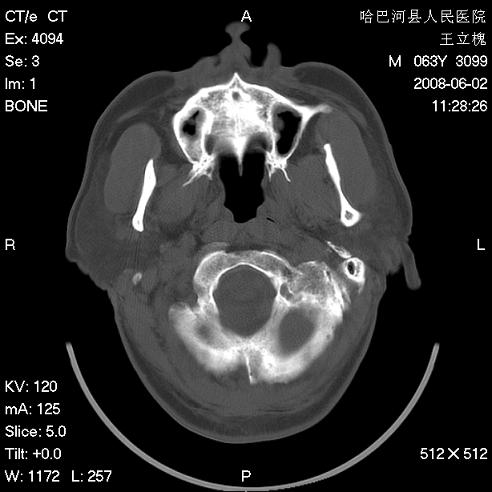

标题: CT13803:反复性鼻塞、流涕一年余 [打印本页]

标题: CT13803:反复性鼻塞、流涕一年余

1.全组副鼻窦炎2.双侧上颌窦积液

.全组副鼻窦炎2.双侧上颌窦积液

1)全副鼻窦炎(左侧上颌窦黏膜下囊肿或息肉)。2)左眼眶肌锥内不规则小结节状软组织密度影;考虑为小血管瘤可能。建议行ct增强扫描检查。

全组副鼻窦炎,左侧肌锥内不规则形软组织肿块影,与眼外肌密度相当,左侧视神经受压,肿块与视神经及眼外肌分界清晰,眼外肌无增粗,眶壁无破坏,球后脂肪间隙不模糊,考虑良性改变,小血管瘤或神经源性肿瘤可能,建议增强扫描。